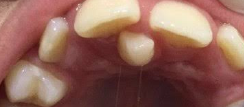

Aparelhos dentários

Alinhar os dentes e corrigir a mordida, proporcionando um sorriso mais harmônico e funcional.”